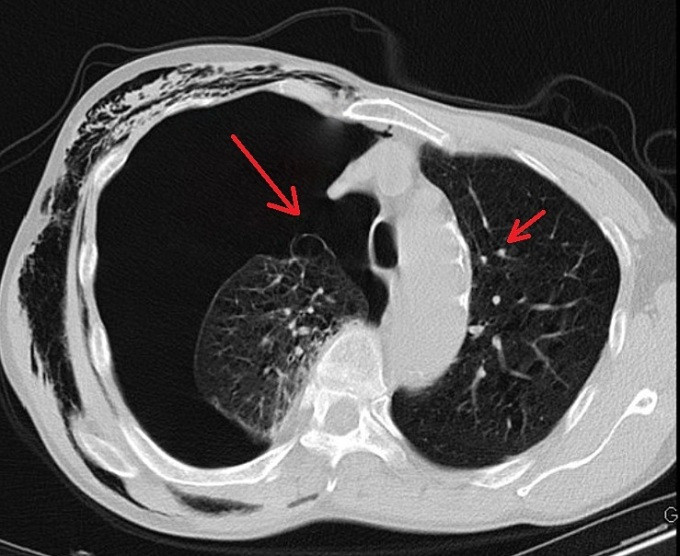

Sau hai ngày điều trị tại khoa Ngoại tổng hợp, tình trạng của ông K. không cải thiện, các bác sĩ chỉ định chụp CT ngực, phát hiện có nhiều kén khí rải rác ở hai bên đỉnh phổi và đáy phổi phải.

Các bác sĩ nhận định đây là trường hợp tràn khí màng phổi do vỡ kén khí, cần phẫu thuật nội soi. Điều này giúp bệnh nhân cải thiện chức năng hô hấp, vận động; tránh các nguy cơ khó thở kéo dài, tràn dịch màng phổi, áp-xe phổi, viêm mủ màng phổi.

Bác sĩ Nguyễn Văn Lâm cho biết kén khí ở phổi là tình trạng đặc trưng bởi sự căng giãn thường xuyên của đường dẫn khí từ tiểu phế quản tận cùng trở xuống, kèm theo có sự phá hủy vách các phế nang không phục hồi.

Kén khí phổi xảy ra cục bộ tại vùng của phổi, có thể một hoặc nhiều kén tập trung ở thùy trên nhiều hơn thùy dưới, thường kết hợp với viêm phế quản mạn tính, giãn phế nang khu trú, lao, hoặc bội nhiễm gây áp-xe phổi…

Bệnh làm tăng khoảng chết sinh lý và gây chèn ép tổ chức phổi lành xung quanh. Nếu không phát hiện, phẫu thuật kịp thời, bệnh sẽ gây xẹp cả phổi ở bên mọc kén, đẩy trung thất ép cả phổi bên đối diện, hậu quả là suy hô hấp rất nặng nề. Thậm chí, nếu tăng áp lực trong đường thở bệnh nhân, kén khí có thể vỡ gây tràn khí màng phổi dẫn tử vong.